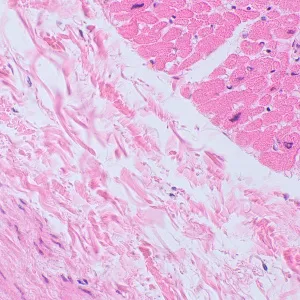

Микроскоп MAGUS Bio 250BL может использоваться и для рутинной работы в лаборатории, и для научных исследований, и для обучения студентов. Он предназначен для работы с тонкими срезами и мазками биологических образцов в проходящем свете. Основной метод наблюдений – светлое поле, но возможно и использование темного поля, поляризованного света и фазового контраста (при установке дополнительных компонентов).